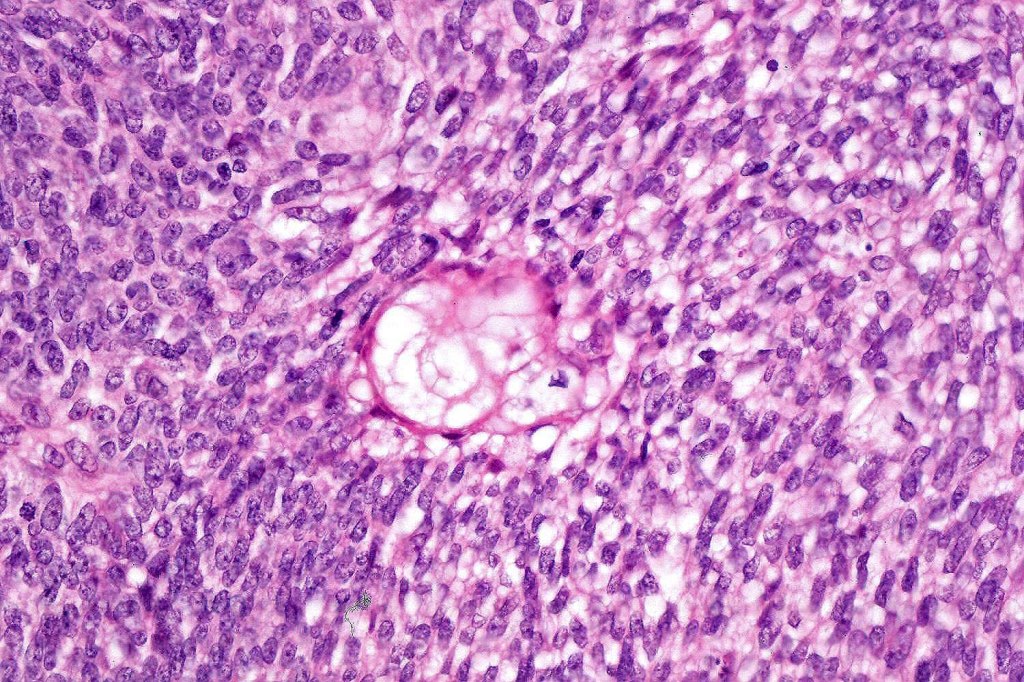

•Comedo type necrosis commonly present

•Tumors are composed of an admixture of darkly staining basaloid cells with hyperchromatic or vesicular nuclei and more obvious sebaceous cells with eosinophilic, bubbly, multivacuolated cytoplasm frequently indenting the nucleus (scalloped)

•Often mitoses are numerous and abnormal forms evident

Sebaceous carcinoma from a patient with Muir-Torre syndrome kindly shared by Dr. Antonina Kalmykova.